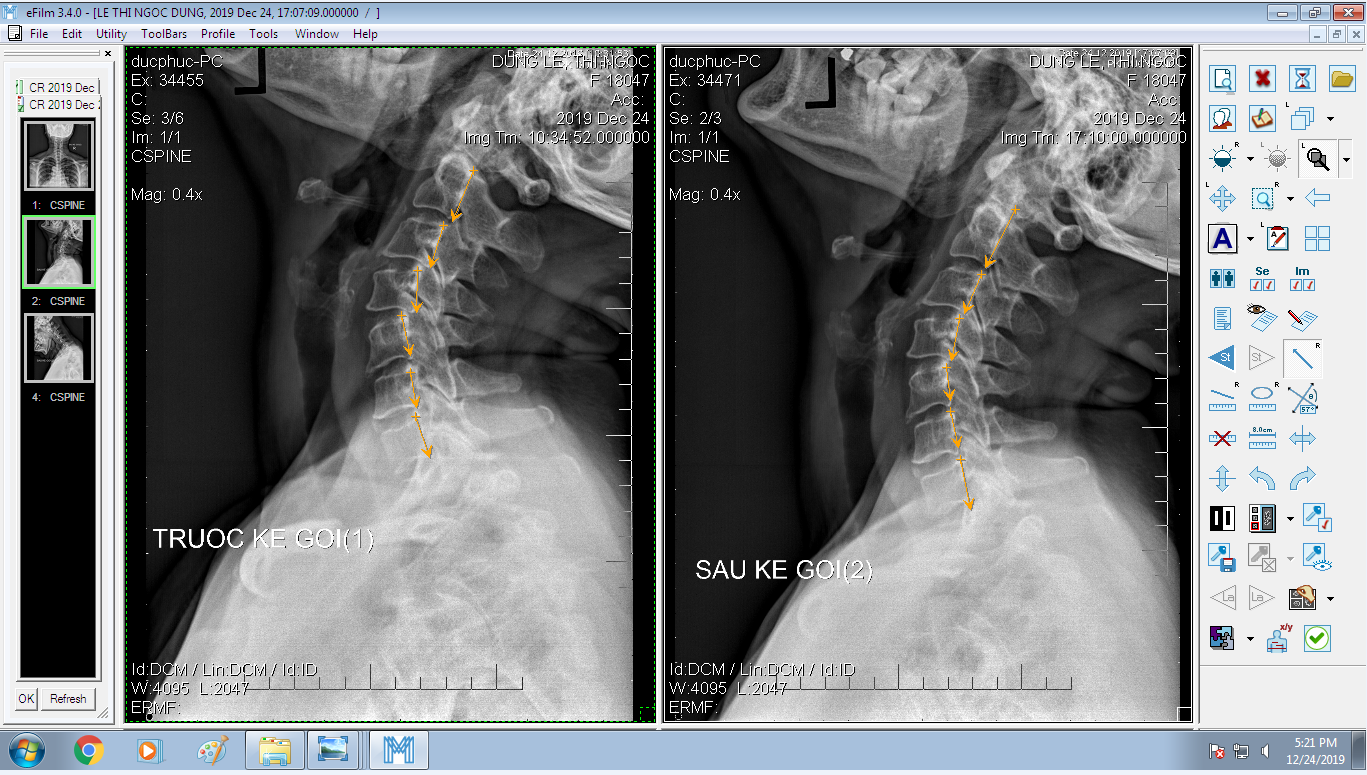

DOCTORLOAN đã thành công trong điều chỉnh xương khớp về đúng vị trí trong thời gian ngắn